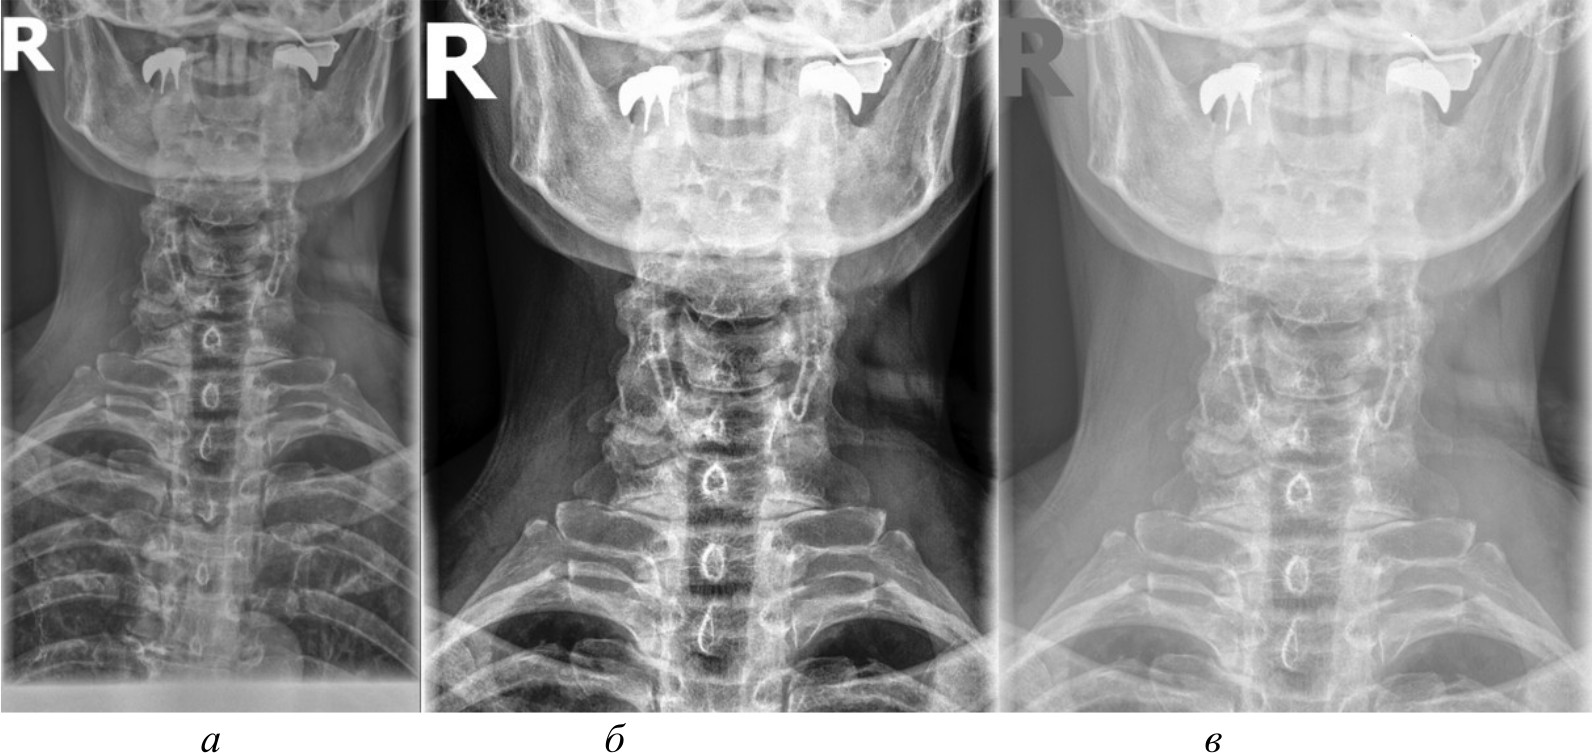

Для создания эталонного набора изображений рентгеновские снимки в формате DICOM были загружены в специализированное программное обеспечение для медицинской визуализации. DICOM является стандартным форматом для медицинских изображений, который позволяет сохранять изображение с высоким качеством и дополнительной информацией об исследовании. Однако для дальнейшей обработки и анализа эти DICOM-файлы конвертируются в более распространенные графические форматы. Специализированное программное обеспечение сохраняет их в формате PNG. На рис. 2, а представлено изображение, полученное в результате работы в специализированном программном обеспечении.

Несмотря на то, что PNG является одним из четких графических форматов, он все же может приводить к некоторой потере качества по сравнению с исходными DICOM-файлами. Поэтому для извлечения более качественных изображений и проведения более детального анализа применяются алгоритмы и методы компьютерного зрения, которые способны работать непосредственно с DICOM-данными, избегая потерь при конвертации.

Для сравнительного анализа использовались различные методы и алгоритмы компьютерного зрения. Помимо изображений в формате PNG, конвертированных из исходных DICOM-файлов, применялись и другие подходы, направленные на извлечение более качественных изображений непосредственно из DICOM-данных, среди которых:

- базовое отображение Python. Изображения загружены в Python и отображены при помощи библиотеки Pillow без применения каких-либо дополнительных преобразований. Данный метод представлен на рис. 2, б;

- медианный фильтр. Для сглаживания шумов и артефактов на изображениях к базовому отображению Python применен медианный фильтр из библиотеки OpenCV. Размер окна фильтра был подобран эмпирически. Данный метод обработки представлен на рис. 2, в;

- адаптивная эквализация гистограммы. Для улучшения локального контраста изображений помимо базового отображения Python использована адаптивная эквализация гистограммы из библиотеки OpenCV. Метод адаптивной эквализации представлен на рис. 3, a;

- стандартная эквализация гистограммы. Для сравнения с адаптивной эквализацией помимо базового отображения Python применена стандартная эквализация гистограммы из OpenCV. Данный метод представлен на рис. 3, б;

- гамма-коррекция. Для регулирования яркости и контрастности изображений, а также для сравнения с двумя предыдущими эквализациями использована гамма-коррекция. Значение гамма-параметра подбиралось эмпирически. Гамма-коррекция представлена на рис. 3, в.

Рис. 2. Изображение, полученное при помощи специализированного программного обеспечения (а), метод базового отображения в Python (б), метод базового отображения Python с применением медианного фильтра (в)

Исходя из полученных изображений при использовании различных методов можно сделать следующие выводы:

- базовое отображение DICOM-данных с помощью библиотеки Pillow показало наличие значительного количества шумов и размытых объектов на полученных изображениях, что затрудняет четкое обнаружение анатомических ориентиров;

- применение медианного фильтра для сглаживания артефактов привело к чрезмерному размытию деталей на изображениях, сделав их еще менее пригодными для дальнейшего анализа;

- использование методов эквализации гистограммы продемонстрировало значительное улучшение контрастности и четкости визуализации анатомических структур по сравнению с базовым отображением и медианной фильтрацией;

- гамма-коррекция изображений, в отличие от эквализации, больше повлияла на яркость, нежели на контрастность, поэтому показала себя хуже в контексте задачи выделения ключевых анатомических ориентиров;

- отображение изображений в формате PNG, полученных из исходных DICOM-данных после применения ряда предварительных обработок с помощью специализированного программного обеспечения, продемонстрировало качество визуализации несколько меньшее, чем у методов эквализации, но при этом превосходящее качество других рассматриваемых методов обработки. В итоге комплекс предварительных обработок, необходимых для конвертации DICOM-данных в формат PNG, позволяет достичь качества визуализации, которое хотя и уступает эквализации, но превосходит другие методы.

Рис. 3. Метод адаптивной эквализации гистограммы, метод стандартной эквализации гистограммы, метод гамма-коррекции